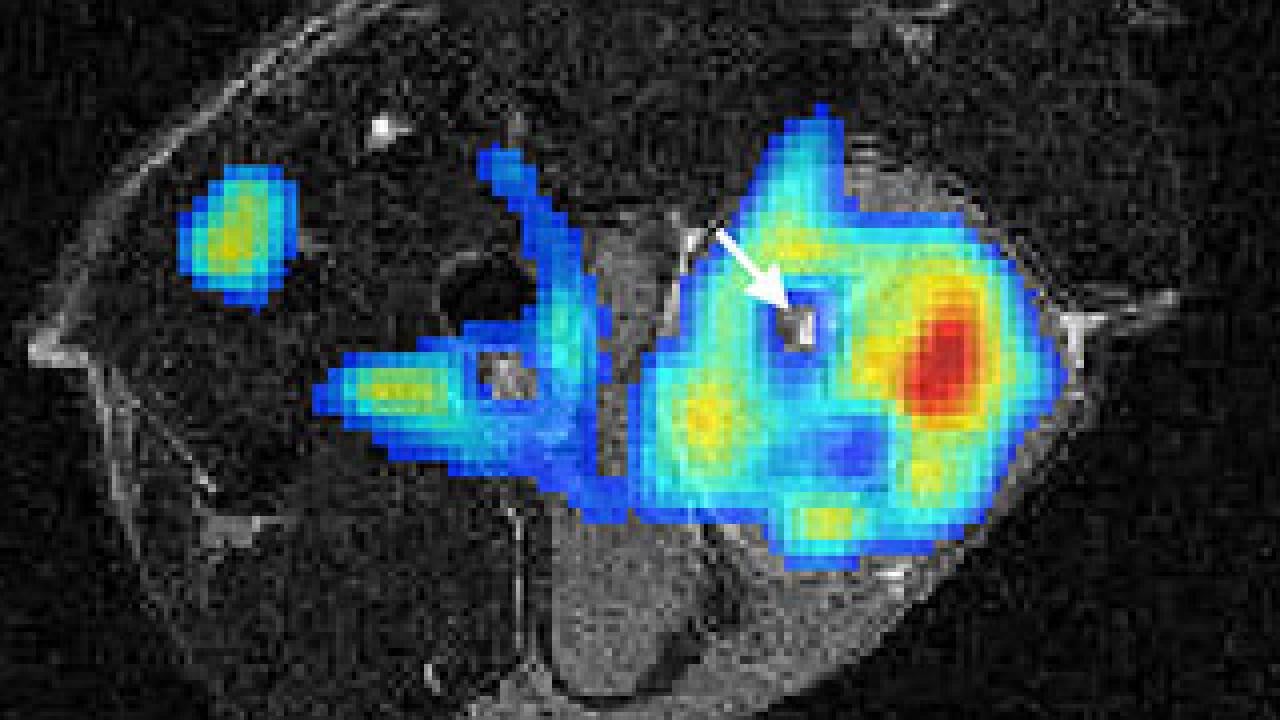

In this combined PET/MRI scan of a tumor in a lab mouse, the colored area is the PET scan image. The arrow points to a hole, probably dying tissue, in the middle of the tumor.

MRI scans provide exquisite structural detail but little functional information, while PET scans -- which follow a radioactive tracer in the body -- can show body processes but not structures, said Simon Cherry, professor and chair of biomedical engineering at UC Davis. Cherry's lab built the scanner for studies with laboratory mice, for example in cancer research.

"We can correlate the structure of a tumor by MRI with the functional information from PET, and understand what's happening inside a tumor," Cherry said.